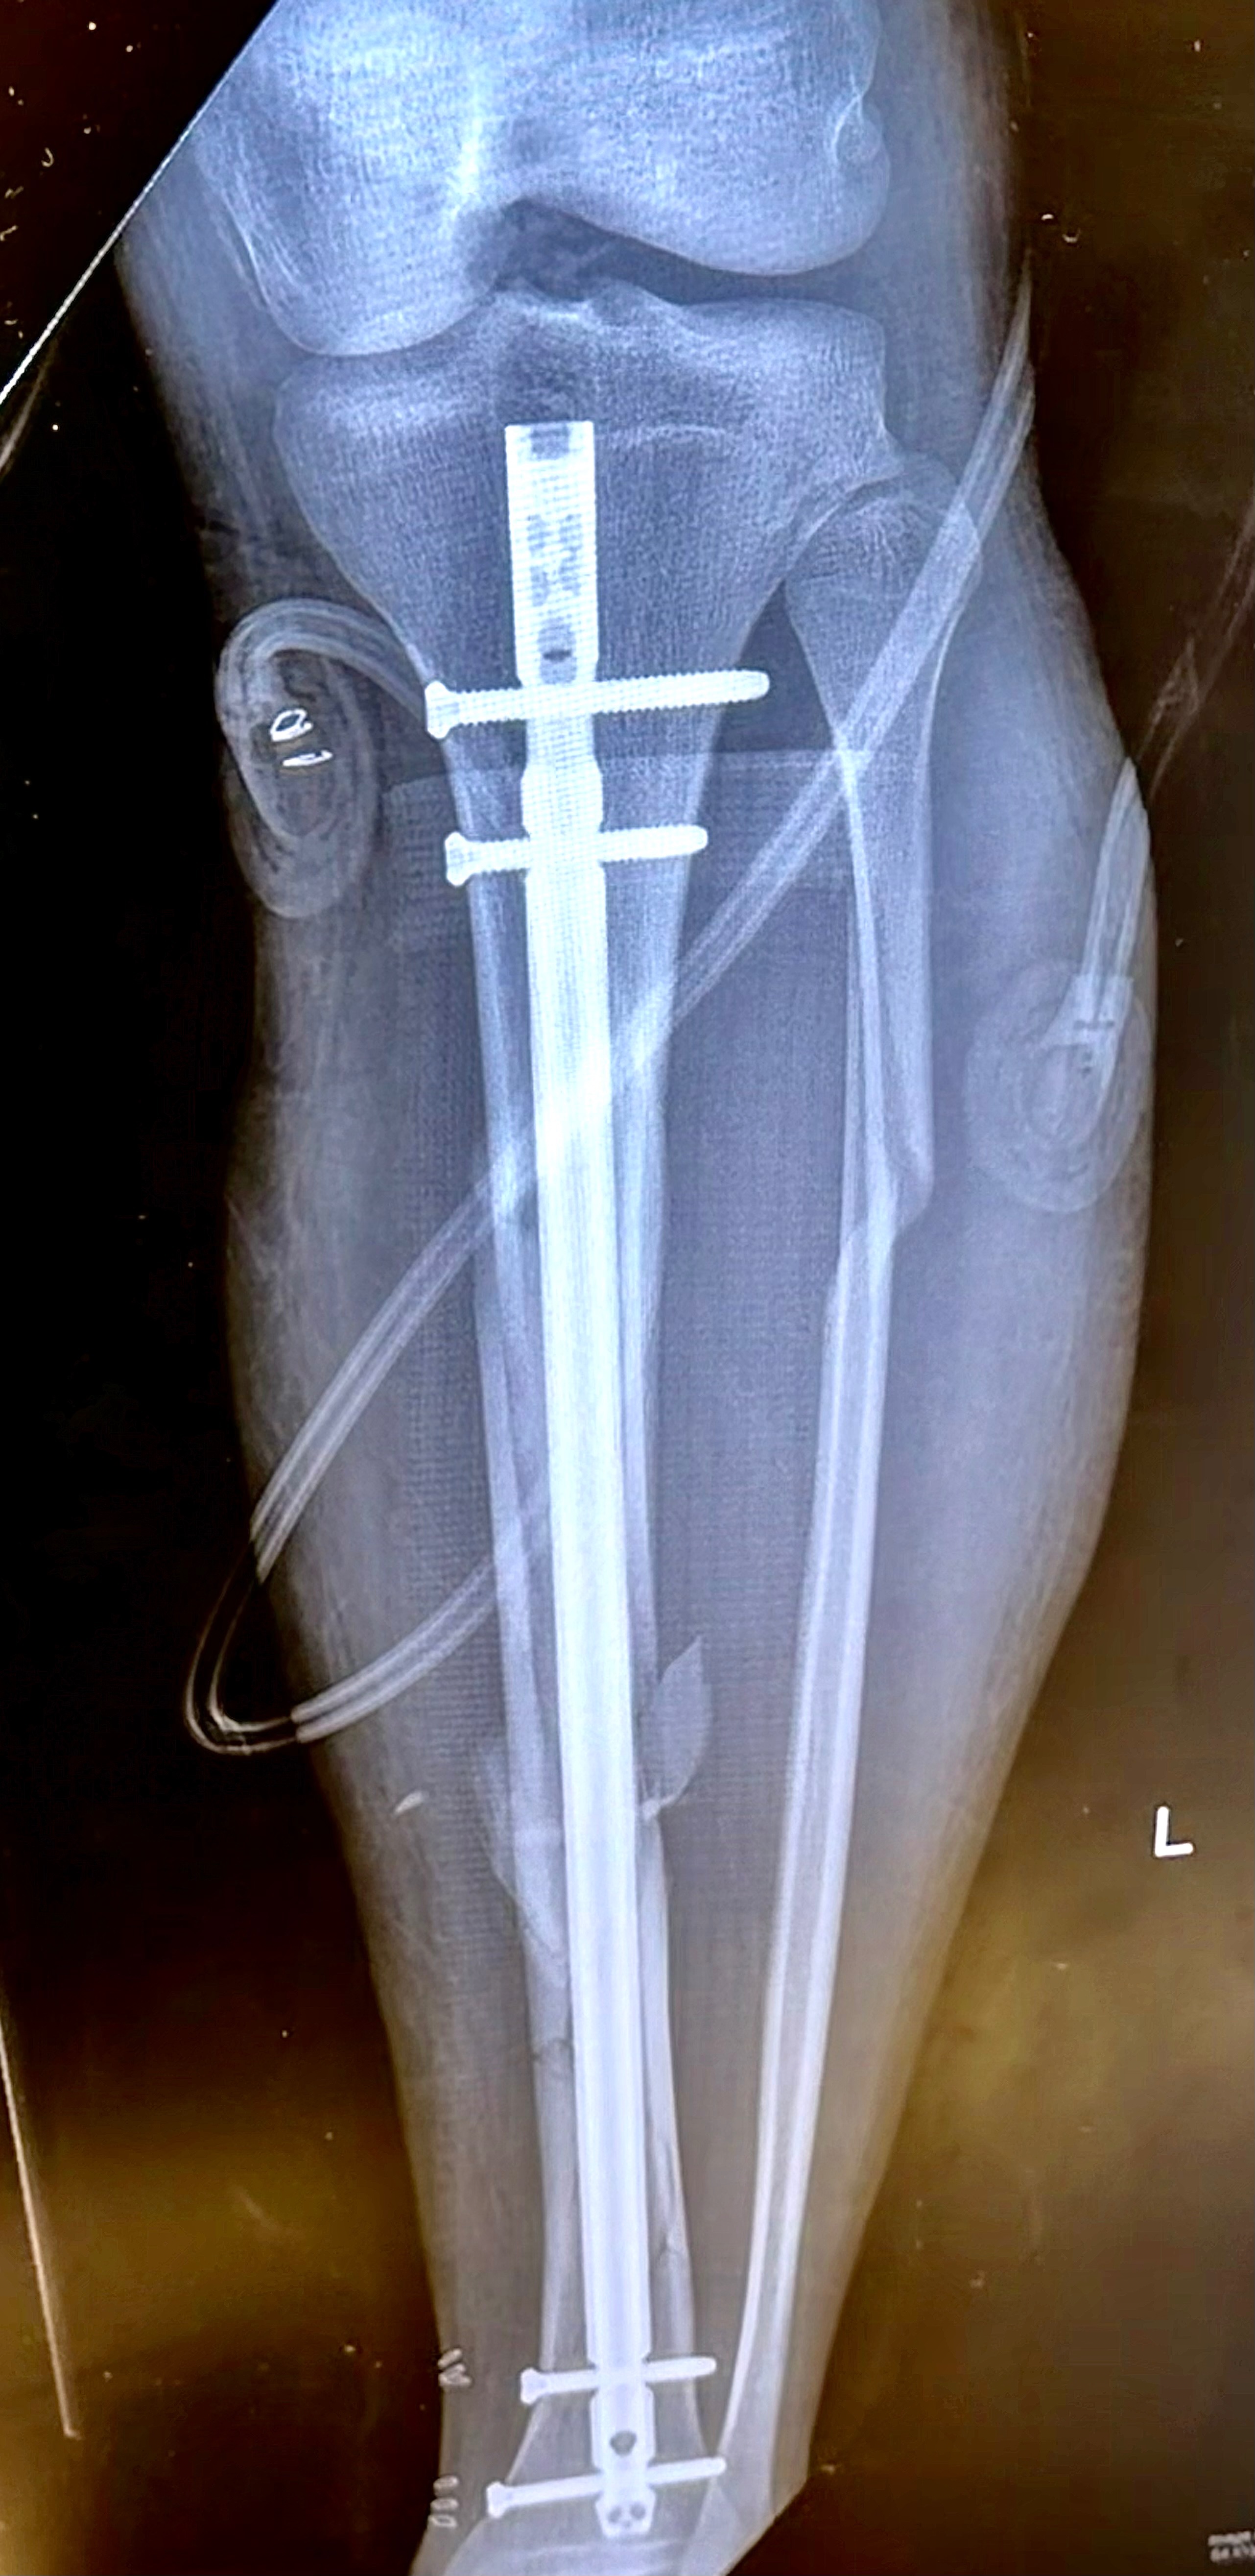

Our son, Cayen Ridge, was recently involved in a serious motorcycle accident after a driver ran a red light and struck him. In an instant, his life was turned upside down literally . After doing 3 front flips through the air somehow his left leg managed to take the brunt of the crash.Iit is truly by God’s grace, Cayen survived, but he is now facing a long road to recovery. While he does have insurance, the reality is that the copays and out-of-pocket medical expenses are overwhelming, with his leg being shattered he has to see the surgeon every two weeks. On top of that, he is currently unable to work, leaving him without a way to keep up with his everyday bills while he heals. He can apply for disability, but we were told by the California police department it could take up to 3months to get his police report back.